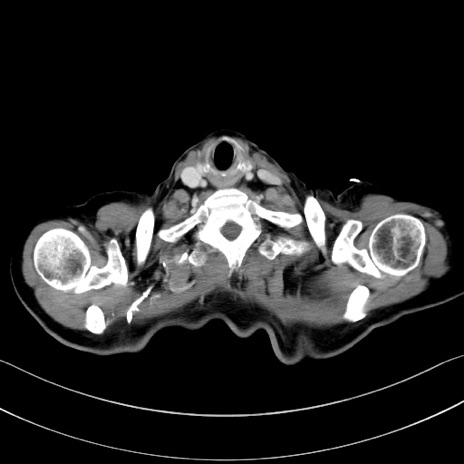

症例28(横断像)

【症例】60歳代男性

【主訴】嘔吐

【現病歴】胃癌にて胃全摘後。食思不振が悪化し、夜中に嘔吐することがある。

【既往歴】胃癌、胃全摘、脾摘、胆摘後

【データ】WBC 5900、CRP 10.56